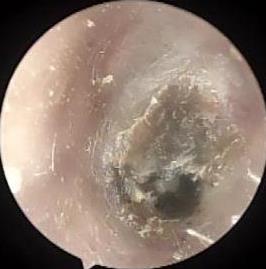

• 耳内镜下耳屏软骨-软骨膜鼓膜修补术后的短期疗效观察

2025, 31(6):1-8. DOI: 10.12235/E20240626

摘要:目的 探讨耳内镜下耳屏软骨-软骨膜鼓膜修补术后的短期疗效。方法 回顾性分析2019年9月-2022年8月该院收治的78例鼓膜穿孔患者的临床资料,患者均采用耳内镜下鼓膜修补术。术后随访3个月,观察鼓膜形态和穿孔愈合情况,记录内镜图像、干耳时间、术前术后听力及耳鸣情况,以及外耳道狭窄等并发症的发生率。结果 术后3个月,鼓膜穿孔愈合率为97.44%(76/78),愈合良好,平均气导听阈较术前明显改善,气骨导间距较术前明显缩小,耳鸣较术前明显改善,差异均有统计学意义(P<0.05)。干耳时间为(4.21±1.12)周。术后出现肉芽5例,再穿孔2例,真菌感染2例,术腔感染、耳屏感染、外耳道狭窄和切口瘢痕各1例,所有患者术后均未发生面神经麻痹和感音神经性聋等严重并发症。结论 耳内镜下耳屏软骨-软骨膜鼓膜修补术是一种安全、有效的手术方法。根据术后愈合规律、内镜下鼓膜和外耳道形态特征,可为鼓膜修补术后正常中耳转归和并发症的诊疗,提供临床参考。